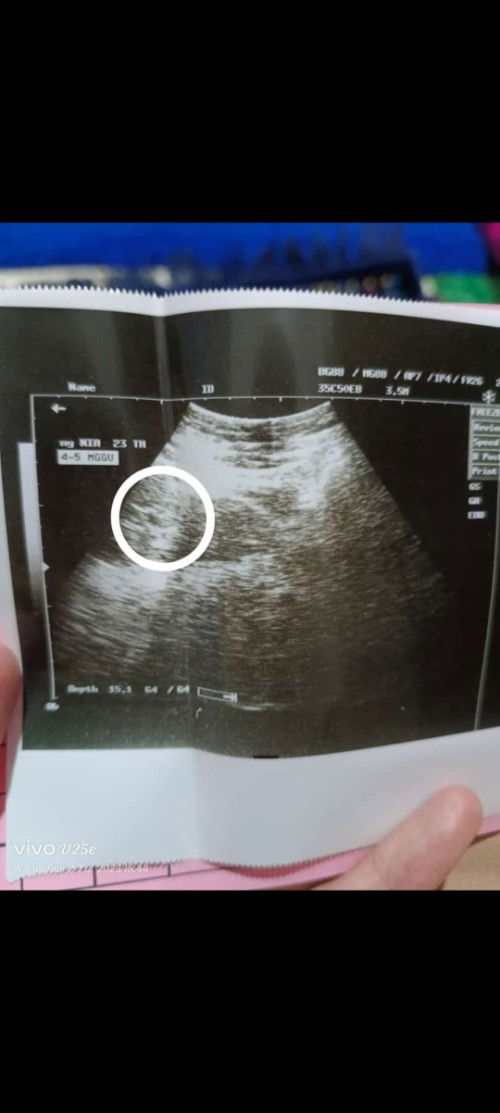

Bun aku mau curhat sediki. saya hamil 5 jalan 6 minggu, hpht 30 Mei. Lalu kemarin pagi pas pipis keluar darah kaya menstruasi, perut mules pinggang panas, udh kebidan + usg , katanya kantung kehamilan masih ada, dan sampai saat ini masih pendarahan kaya org haid, di kasih obat penguat kandungan sama folamil sama suruh bedrest total. Tp disini saya pasrah aja kl emng misal nya yg terbaik semoga janin nya sehat dan kuat bertahan di dalam rahim ku, namun bila mana belum saat nya aku punya anak ke 2 aku ikhlas, semoga di kehamilan selanjut nya sehat2 dan mulus lancar hingga persalinan , doakan aku ya bun.. 🤲 Ada kah bunda2 disini yg punya pengalaman hampir sama kaya aku#bantusharing